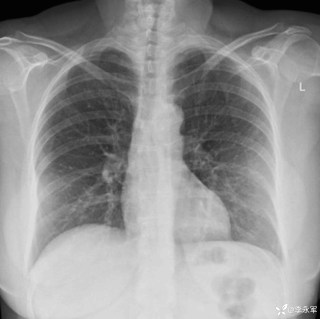

整个右侧胸腔被滚烫的铝水烧穿,多根肋骨骨折、碳化、坏死,背腹部和面部也有大面积烧伤……右肺完全暴露在外,被压缩到只剩一半的体积。这样的病人,还救得活吗?300℃ 铝水烧了 10 分钟,整个右胸都烧穿了时间拨回到 2024 年 9 月 26 日,下午 15 点,救护车的警笛声撕破了浙江大学医学院附属第二医院(文内简称「浙大二院」)解放路院区的平静。警笛声由远及近,停在了急诊的门口。不多时,一群人冲进急诊。「300 多度的铝水烧了 10 分钟,整个右胸都烧穿了!」负责转运的同事几乎是咆哮着喊出这句话。急诊医学科的许永安主任医师看到患者情形时,心下一惊。本该完整的右侧胸腔,现在成了一个焦黑的大洞,大